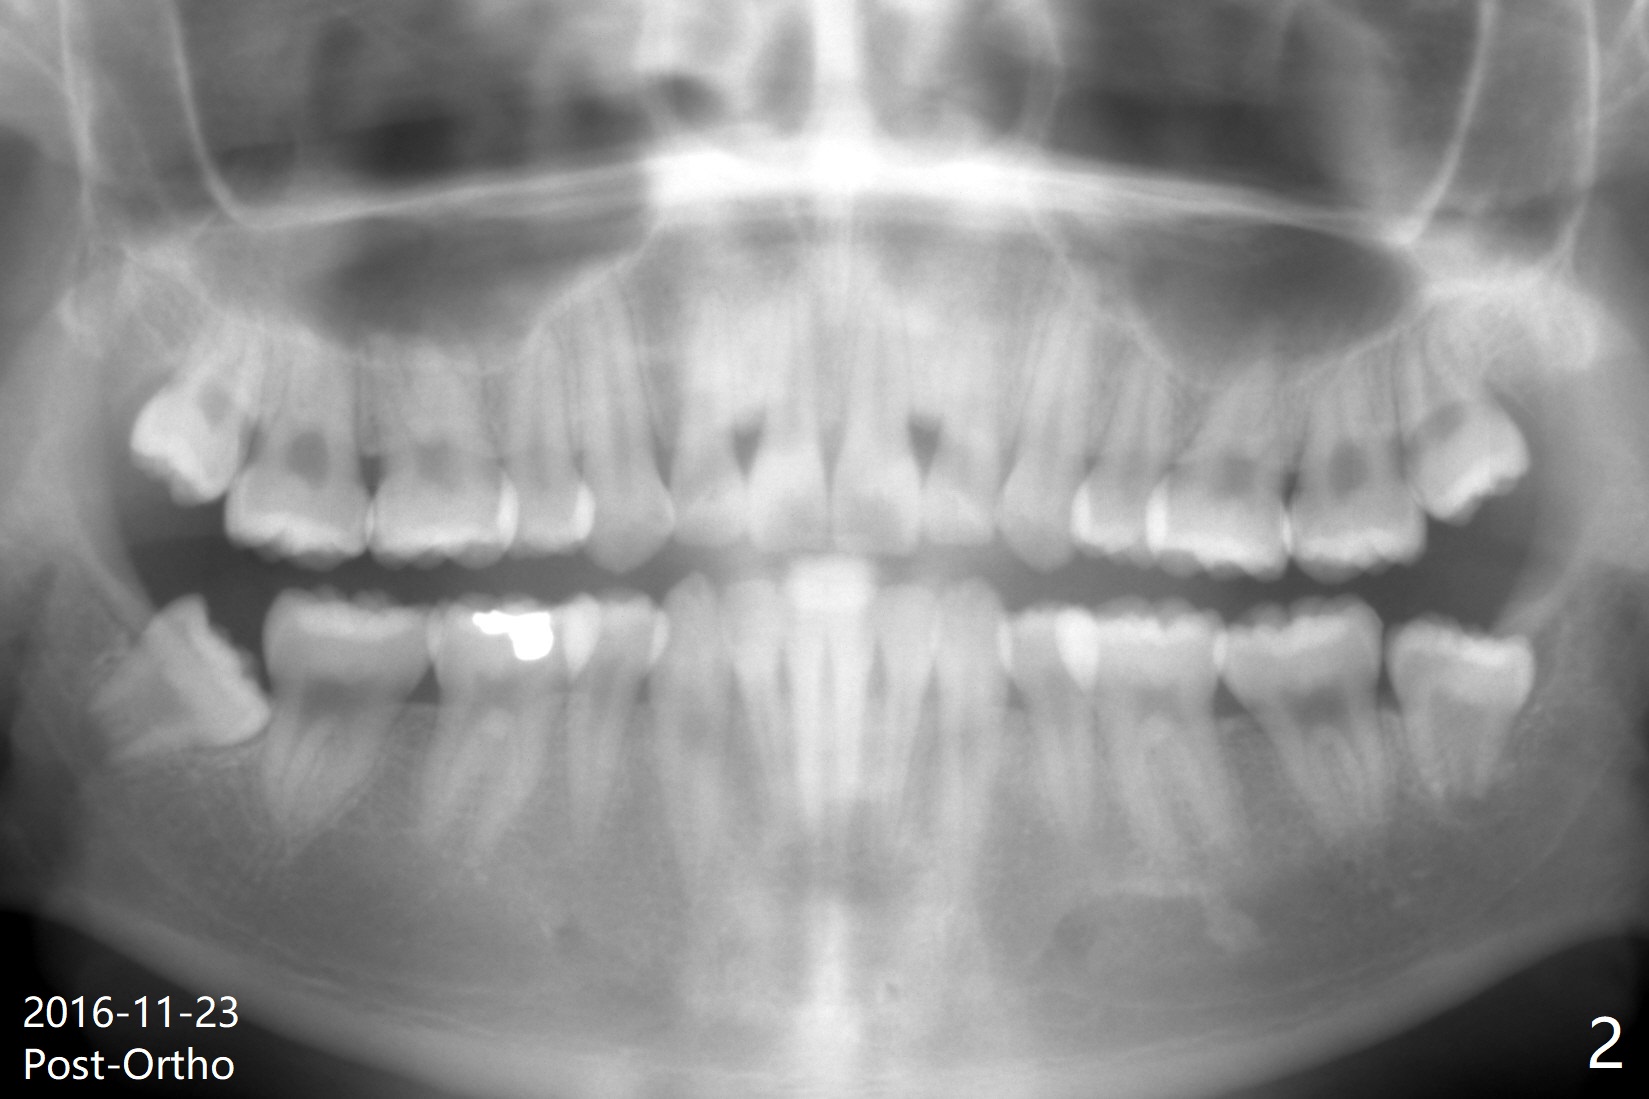

A 19-year-old man with history of orthodontic treatment (Fig.1,2) returns to office for #1,16,17,32 extraction with Collagen Plug placement at #17 and 32 (4-0 plain gut suture). The sockets heal in 4.5 months (Fig.3).